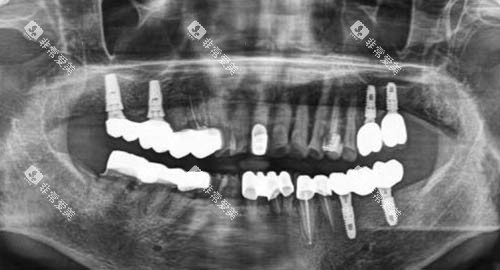

为了给患者提供更比较准、较高的效率的治疗,重庆美奥口腔医院引进了一系列国内外靠前的诊疗设备。

例如,智能化口腔全景机能够快速、较准地拍摄口腔全景图像,为医师的诊断提供详细的依据;种植牙导航系统则可以在种植手术中实现比较准定位,大大提高了种植手术的成功几率和靠谱性。

例如,在口腔种植方面,医院采用靠前的种植技术和优质的种植体,为缺失牙患者修复牙齿功能和美观;在口腔正畸方面,提供传统金属矫正、陶瓷矫正、隐形矫正等多种矫正方式,满足不同患者的需求。